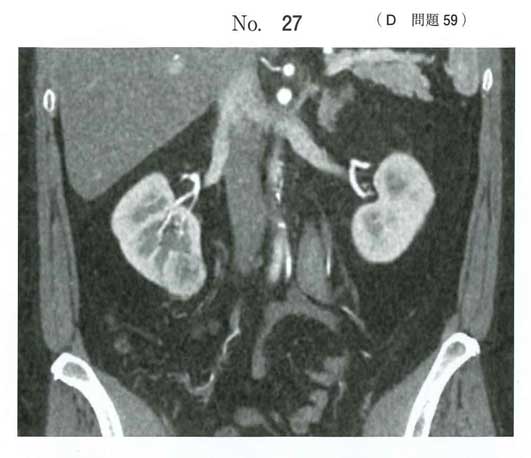

cT1aN0M0の腎細胞癌として腎部分切除術が第一選択かな

NCCNガイドラインではSBRTも選択に入っています

bです。